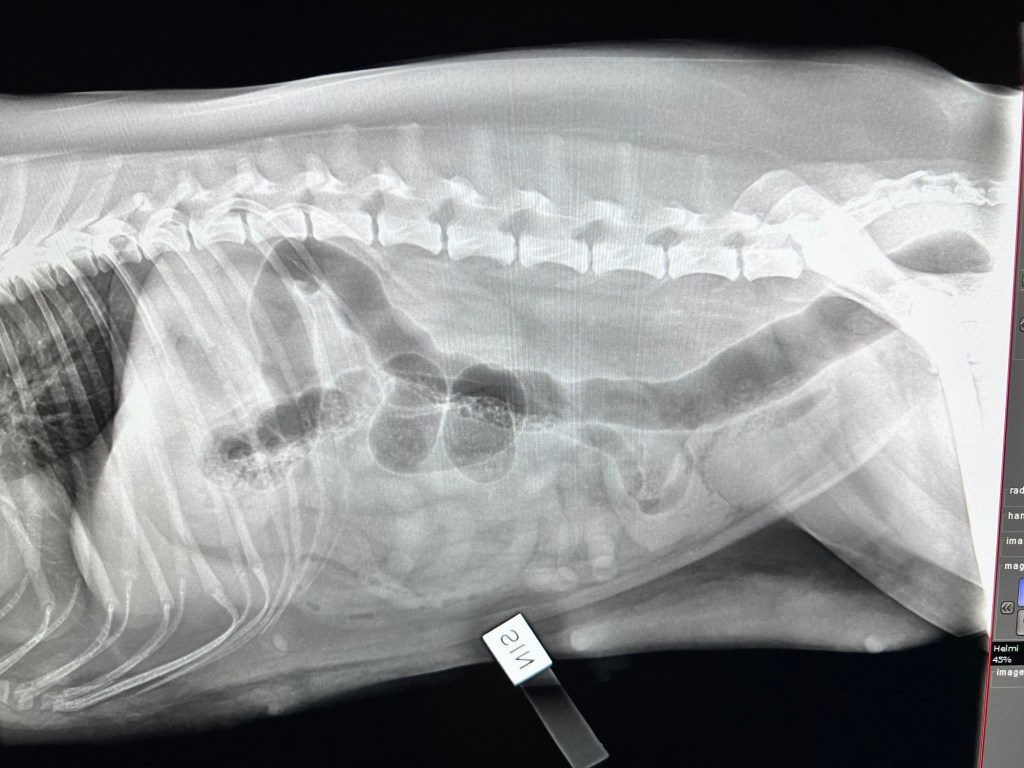

Publicerad den april 19, 2024 av Snömarkens Det blev inga valpisar denna gång med Helmi och Sheldon 💔 Nästa försök vår25 Dela detta: Dela på X (Öppnas i ett nytt fönster) X Dela på Facebook (Öppnas i ett nytt fönster) Facebook Gilla Laddar in … Relaterade